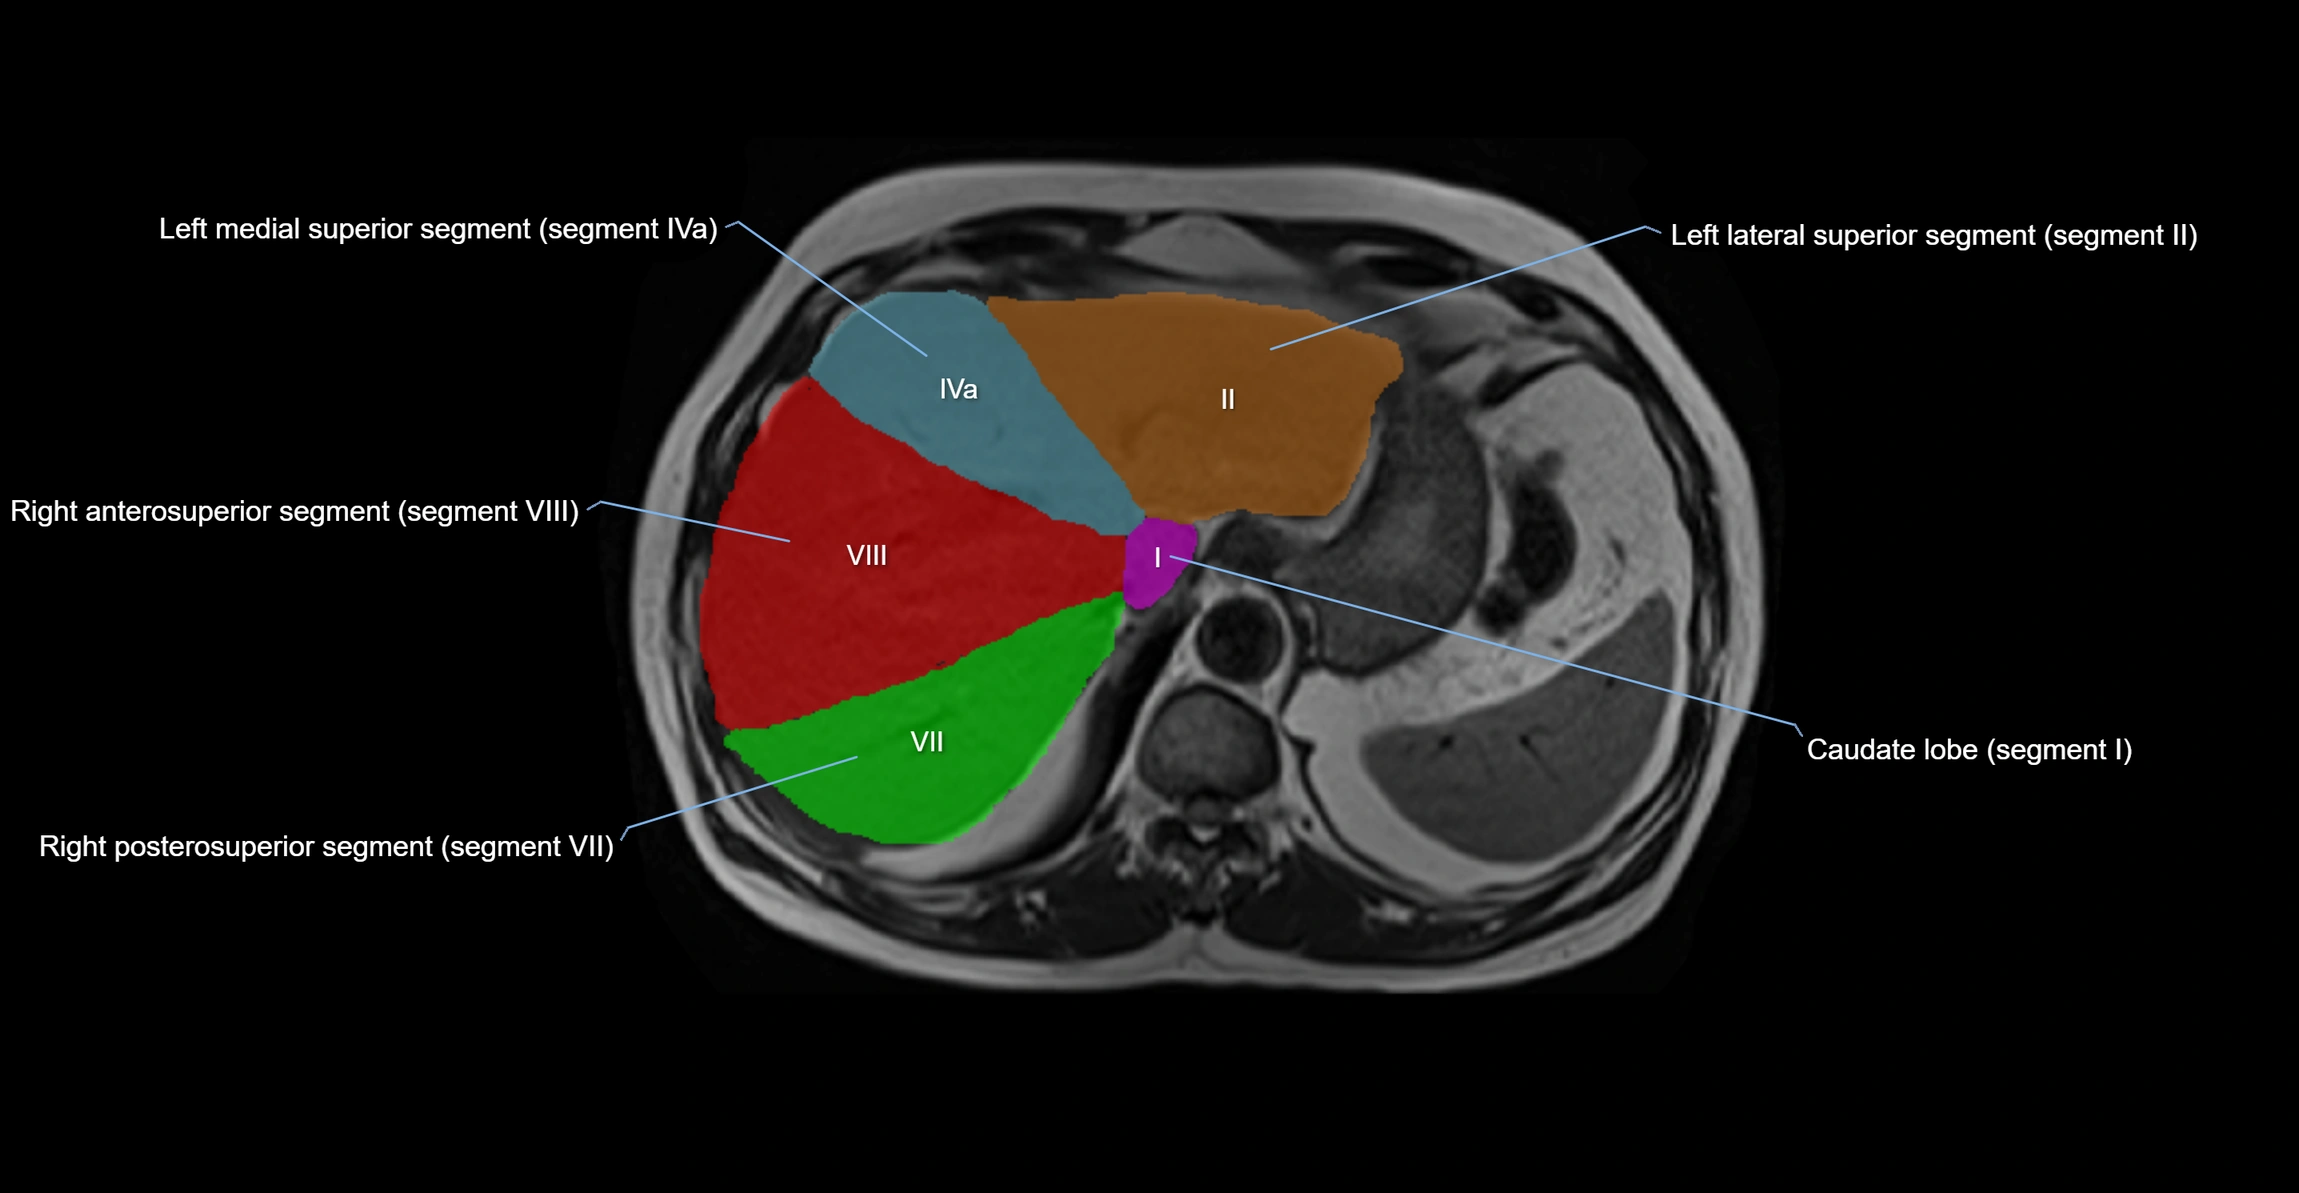

The caudate lobe of the liver is a distinct anatomical subdivision of the liver, designated as segment I in Couinaud’s classification. It lies on the posterior surface of the liver, between the fissure for the ligamentum venosum (left boundary) and the groove for the inferior vena cava (IVC) (right boundary). Superiorly, it is related to the posterior liver surface, and inferiorly it is separated from the left lobe by the porta hepatis.

The caudate lobe is unique because it receives dual portal venous and arterial inflow from both the right and left portal veins and hepatic arteries. It also has independent venous drainage directly into the IVC via multiple small hepatic veins, unlike other lobes that drain through the three main hepatic veins.

This anatomical autonomy makes the caudate lobe especially significant in liver surgery, transplantation, and hepatic venous outflow obstruction syndromes (e.g., Budd–Chiari syndrome). Enlargement of the caudate lobe is a characteristic imaging feature in chronic liver disease and cirrhosis.

• Segment I (Couinaud classification)